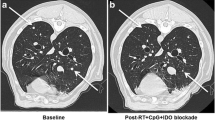

All dogs tolerated hgp100-ATCV vaccination well. The mean age of dogs entered into this trial was 12 years (median 11.5, range 6–16) and the mean weight was 26.1 kg (median 26.7, range 6–52). There were 25 dogs diagnosed with oral melanoma, eight dogs with subungual melanoma, and one dog with cutaneous melanoma. Thirteen dogs were stage II, 7 Stage III and 14 were stage IV. Of these 34 dogs, there were eight Labrador retrievers, four Cocker spaniels, three Golden retrievers, three Chow, three mix breed, three each of Airedale and Newfoundland, and one each of Standard poodle, Miniature poodle, Doberman, Schnauzer, Australian shepherd, Cairn terrier, Rottweiler, Sharpei, and Beagle. Table 2 shows the survival characteristics, clinical stage, and follow-up information on the 34 dogs in this trial. Adverse reactions were limited to mild induration and erythema at the site of vaccination. Systemic toxicities, vitiligo, or autoimmune reactivity against normal melanocytes were not observed with the exception that one dog (#12) developed depigmentation of his oral tumor and some degree of depigmentation of the oral mucosa. This same dog had a complete response to ATCV and remains free of disease at the time of this report (853 days post-initiation of vaccine treatment). Of the 34 dogs that were entered into this trial, 25 died due to progressive disease, two are alive as of the manuscript preparation date (one had a complete response and remains free of disease, and one had a partial response defined as greater than a 50% reduction in tumor volume), six were lost to follow-up (after progressive disease was noted), and one dog died of an unrelated cause (histologic evidence of regional lymph node metastasis was found at the time of death). Objective evidence of tumor regression (one complete response and five partial responses) was observed in six of the 34 dogs (17.6% objective response rate), as determined by three dimensional tumor measurements. Additionally, six dogs experienced SD for a minimum of six weeks for a tumor control rate (CR/PR/SD) of 35.3%. Tumor stage did not correlate with the likelihood of tumor control (Fisher’s; II vs. IV, P=0.71; II vs. III/IV, P=1.00; II/III vs. IV, P=0.73; III vs. IV, P=1.00). Table 3 presents time to progression and overall survival times. Figure 5a, b show the Kaplan–Meier-generated curves for time to progressive disease (median=170 days) for dogs that had tumor control (CR/PR/SD), and overall survival time for dogs having tumor control (CR/PR/SD) or no response. Dogs experiencing tumor control survived significantly longer than dogs having no response (337 days vs. 95 days; P=0.0014).